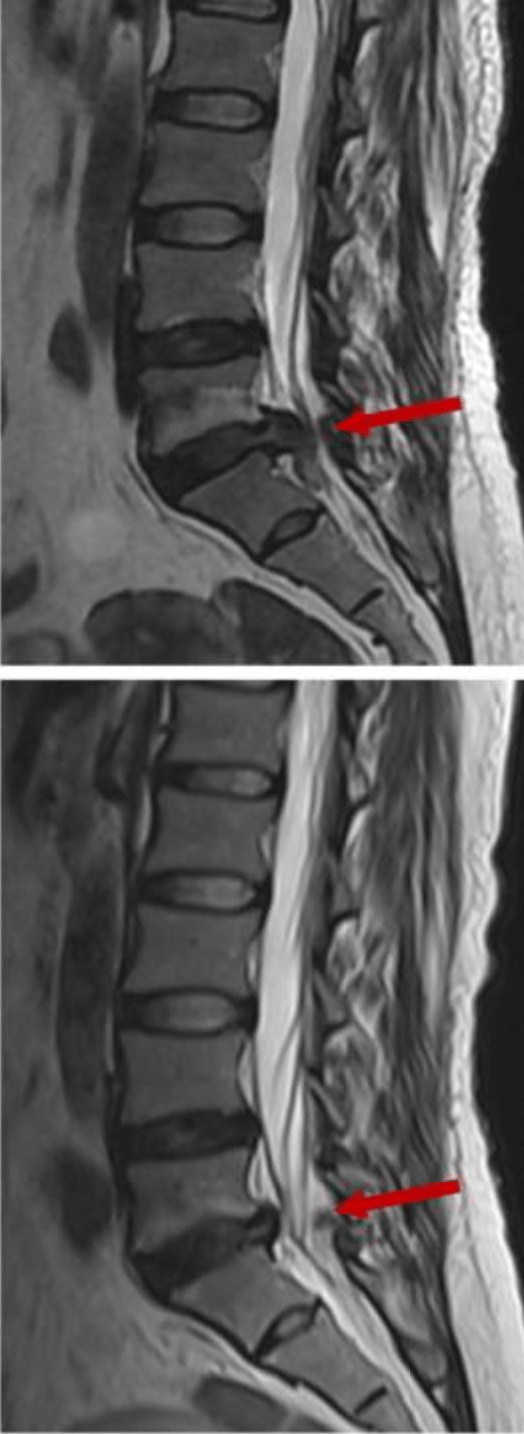

Tipo de hernia: las hernias extruidas o secuestradas (cuando el material se ha desplazado fuera del disco) tienen mayor probabilidad de reabsorción, ya que el sistema inmune puede acceder más fácilmente a ese tejido.

En cambio, las protrusiones discales (cuando el disco solo se abomba sin romperse) tienden a ser más estables y menos propensas a reabsorberse, aunque también pueden mejorar clínicamente con tratamiento conservador. El siguiente dibujo muestra la probabilidad de reabsorción según el tamaño de la hernia.